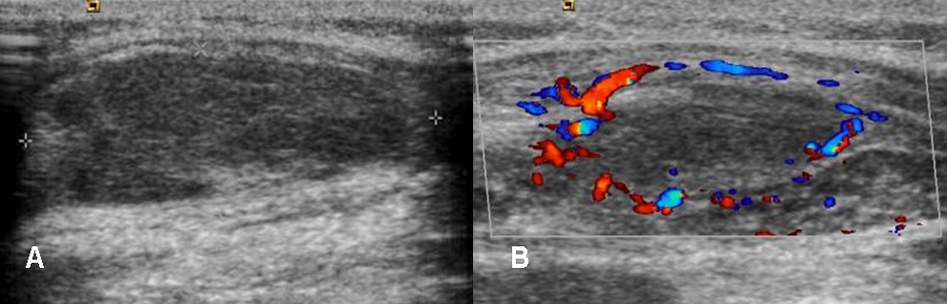

Fig 19. Absceso.

A: Ecografía. Lesión ovalada e hipoecoica con relación a la grasa, en los tejidos blandos.

B: Ecografía doppler. Los bordes de la lesión tienen aumento de su vascularización y corresponde a la formación de un absceso, en su fase inicial.